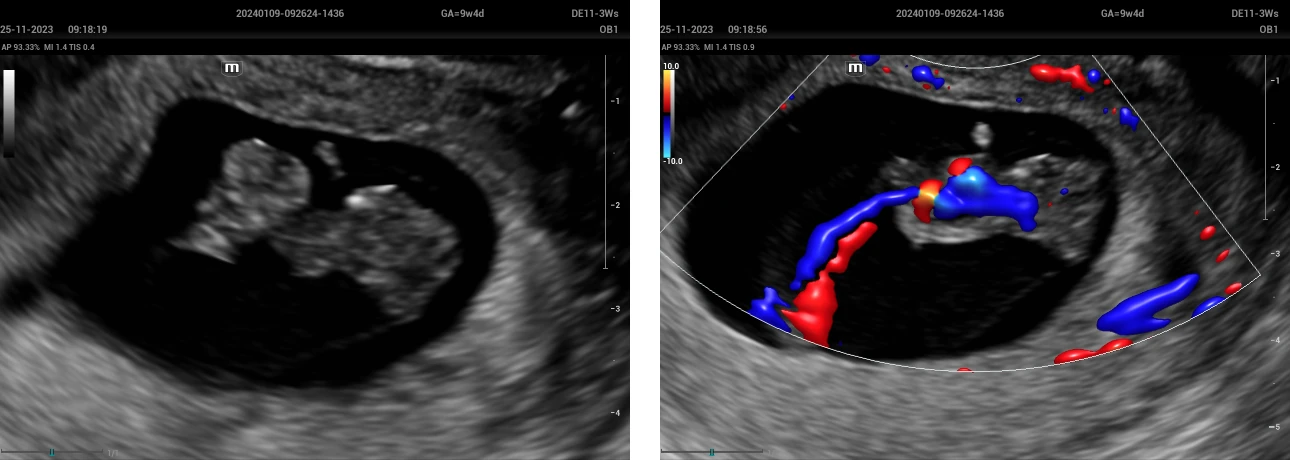

A woman of 22 years old, first pregnancy, marital status domestic partner, level education secondary schooling. The medical history includes a laparoscopic cholecystectomy 3 years ago and the first sexual relationship at the age of 15. The patient went to the Fetal Medicine Service of the Perinatal Maternal National Institute with a private ultrasound exam in which they consider a 9-week gestation + pleural effusion, so she was scheduled for a transvaginal ultrasound, which was performed with an Ultrasound System, model Nuewa I9 (Mindray) with an endocavitary volume transducer DE11-3Ws, observing a 26 mm CRL embryo, with cardiac activity of 171 B.P.M. who presents anencephaly (Figure 1), omphalocele (Figure 2), ectopia cordis (figure 3), hydrothorax and scoliosis (figure 4); Therefore, Body stalk is diagnosed, suggesting the interruption of the pregnancy as there is no prognosis for extrauterine life.

Ectopia cordis

Figure 3: Ectopia cordis

Kyphoscoliosis

Figure 4: Kyphoscoliosis